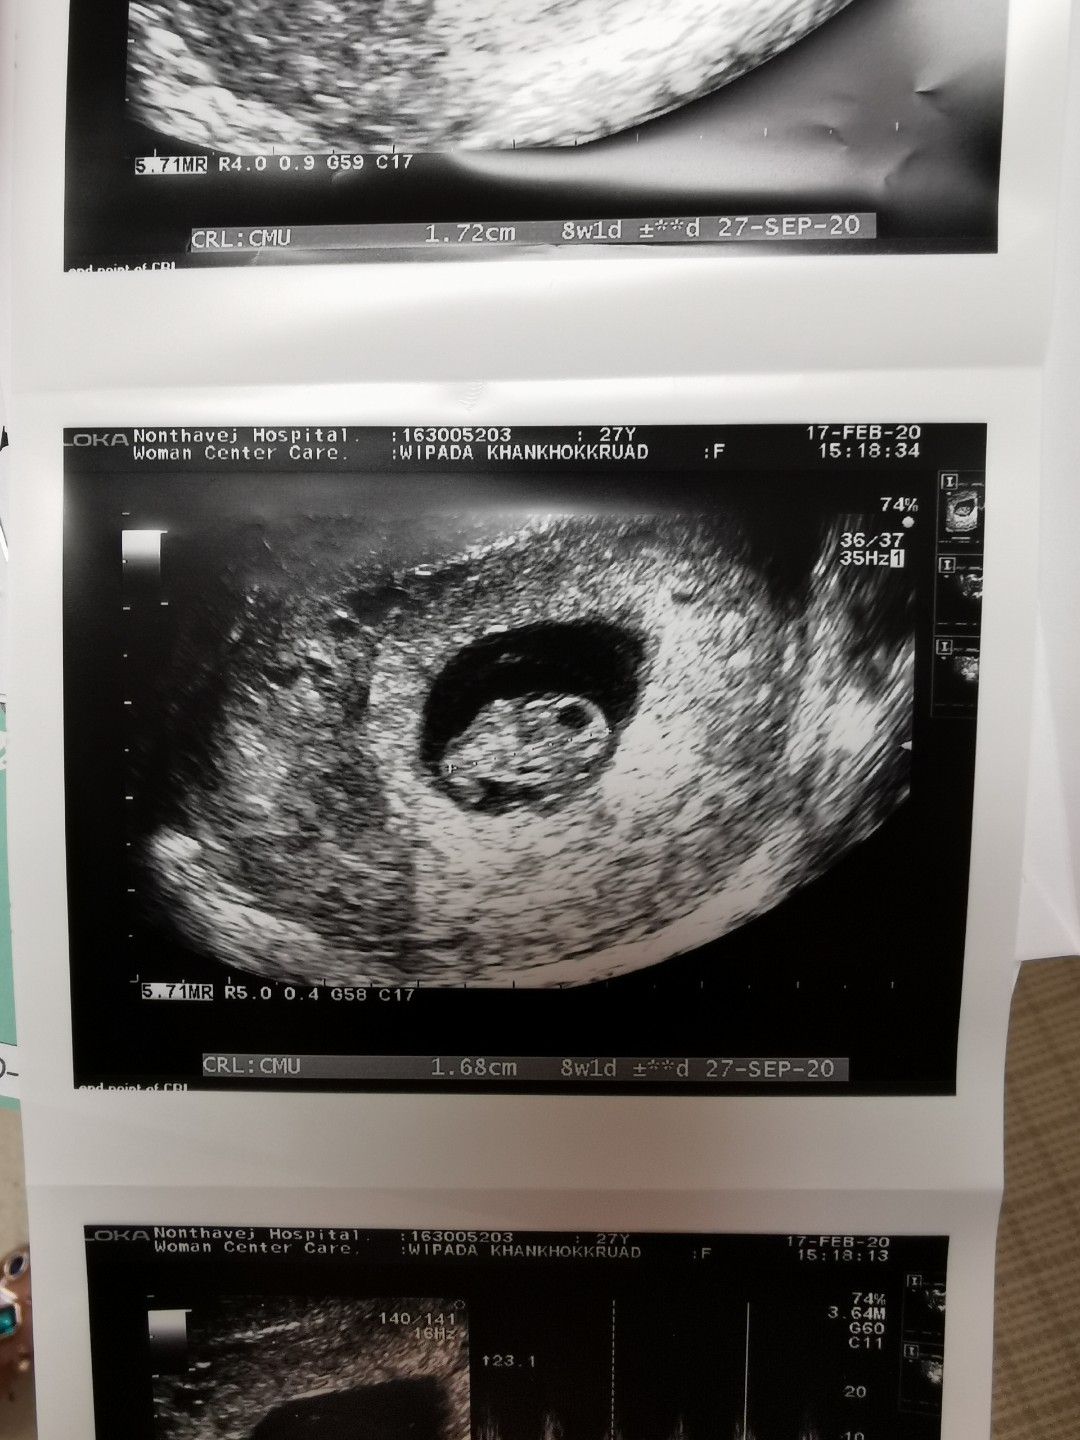

10w1d ท้องป่องอยู่ค่ะ (ภาพคุณแม่ซาวด์ตอน8w1d)🥰